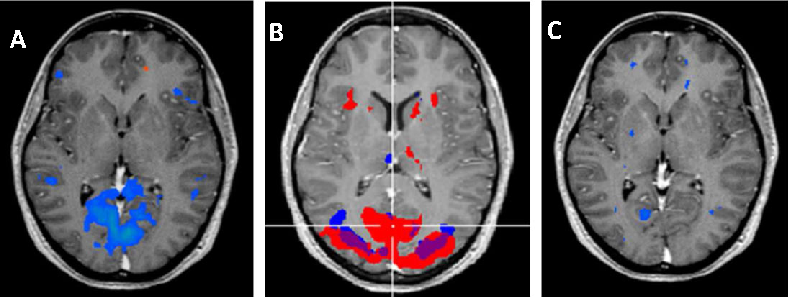

Brain imaging studies demonstrate that elevated homocysteine is associated with accelerated rates of brain atrophy, particularly in medial temporal lobe structures critical for memory. B-vitamin treatment appears to slow this atrophy in individuals with elevated baseline homocysteine.

Homocysteine and Dementia: An International Consensus Statement.